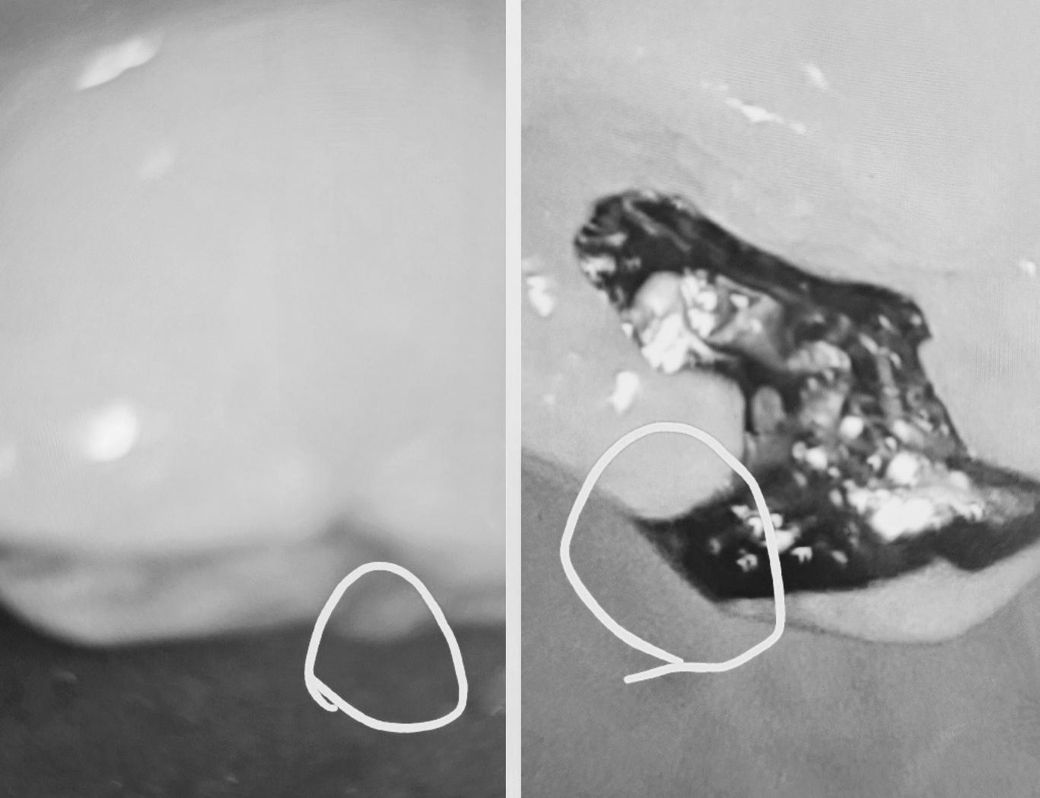

왼ㅡ자연치어금니

오ㅡ인레이 어금니 동일한 어금니 입니다

교합점 및 교두가 삭제된것인가요?

동그라미표시도 봐주세요

자연치 교두는 삭제가 된거 같진 않고, 인레이는 교두 부위에 충치가 잇어서 삭제가 된것같습니다.